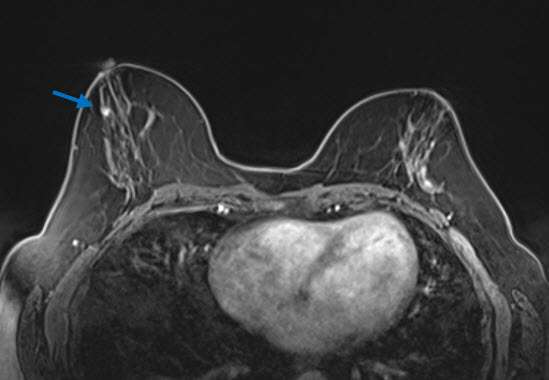

MRI:

Radial sclerosing lesions may also be occult on MRI. When they are identified, they most commonly present as an irregular enhancing mass, which appears similar to carcinoma in morphology and enhancement characteristics (2). They may also present as an architectural distortion with no to mild enhancement, a benign appearing oval or round mass with mild and gradual enhancement, an enhancing focus, or non-mass enhancement (3)(Fig 3). While MRI examinations cannot reliably distinguish RSLs from carcinoma, these exams play an important role in excluding the presence of additional lesions in the affected or contralateral breast.